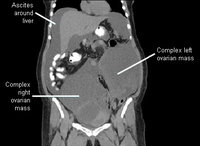

Ovarian masses and ascites on coronal CT

From the collection of Justin C. Chura, MD, Cancer Treatment Centers of America, Philadelphia, PA